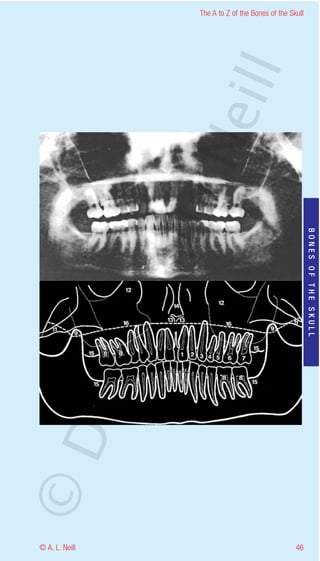

The A to Z of the Bones of the Skull

Mandible Anterior

eill

radiology

orthopantomogram = OPG

Used to show mandibular fractures and an overview of

sinuses and complete dentition

1           Central incisor

2           Lateral incisor

3           Canine

4           First premolar

5           Second premolar

6           First molar

BONES OF THE SKULL

7           Second molar

8           Pulp chamber

9           Coronoid process

10          Head of mandible

ma

11          Zygoma

12          Maxillary sinus

13          Anterior nasal spine of maxilla

14          Vomer (nasal septum)

15          Sites for the third molar

rA

16          Hard palate